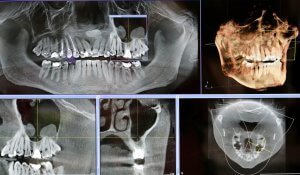

Grillo Dental provides a wide range of services that can be completed all in one office—from general dentistry services for the entire family to dental implants and full-mouth rejuvenation. The office is fully equipped with high-tech equipment and tools, enabling the doctors to treat even the most complex of cases.